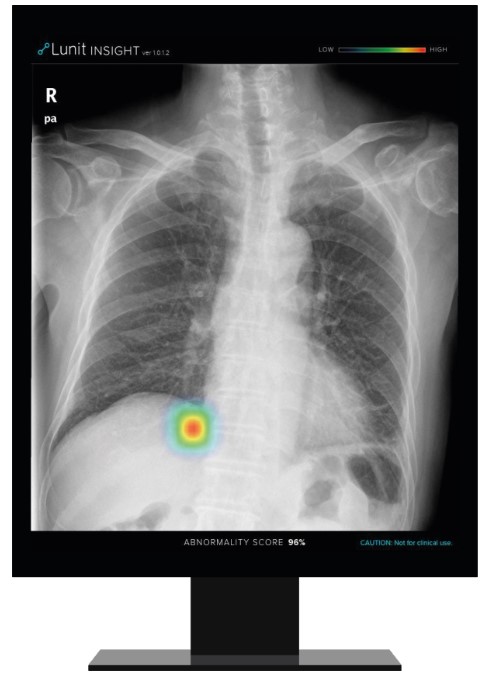

루닛의 폐질환 진단 보조 소프트웨어 ‘루닛 인사이트 CXR.’ [사진 = 루닛]

루닛은 최근 필립스(Philips) 본사와 파트너십을 체결했다. 이번 파트너십으로 루닛의 폐질환 진단 보조 소프트웨어 '루닛 인사이트 CXR'은 필립스의 흉부 엑스레이 진단 플랫폼에 탑재돼 전 세계 의료 현장에 공급된다. 필립스는 GE 헬스케어, 지멘스와 함께 세계 3대 의료기기 기업으로 꼽힌다. 업계에 따르면 필립스의 글로벌 흉부 엑스레이 시장 점유율은 20% 가량에 달한다. 다안 반 마넨(Daan Van Manen) 필립스 진단용 엑스레이 부문 총괄 매니저는 루닛의 기술력에 대해 "루닛 AI 알고리즘의 판독 정확도와 효율성은 이미 국제 학술지 등을 통해 입증됐다"고 평가했다.